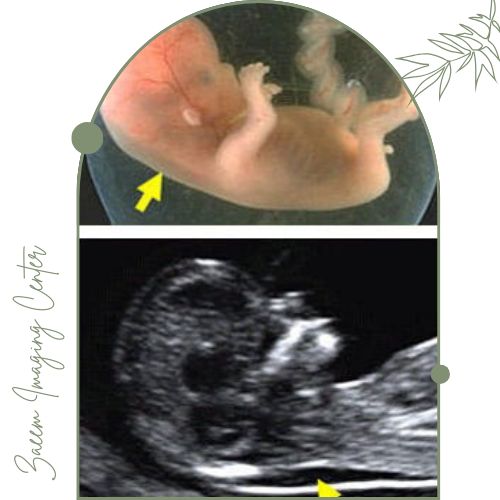

در این مرکز از دستگاههای پیشرفته سونوگرافی ویژه NT استفاده میشود. این تجهیزات تصویری کاملاً واضح از ضخامت شفاف پشت گردن جنین (NT) و سایر شاخصهای مهم سلامت جنین بهدست میدهند که نقش کلیدی در تشخیص سریع و دقیق اختلالات ژنتیکی دارند.اطلاعات جمعآوری شده توسط متخصصان با بالاترین استانداردها تحلیل و گزارش میشود تا مادران با اطمینان روند بارداری را طی کنند.